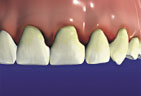

Gingivitis Gingivitis

(bleeding gums)